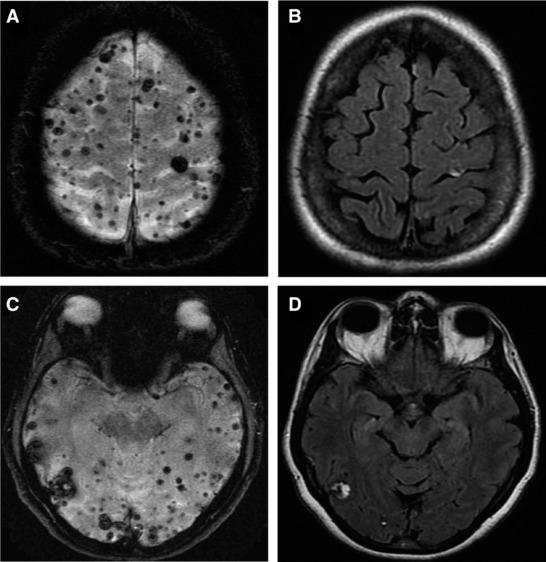

ALK肺癌即肺癌細胞出現了「間變性淋巴瘤激酶基因變異」。八成肺癌患者屬非小細胞癌,而當中約5%為ALK肺癌。目前有三代ALK抑制劑,雖然第二代藥物在治療腦轉移成效較第一代為佳,但對於出現腦轉移患者的預後仍不理想。中大醫學院腫瘤科學系系主任兼李樹芬醫學基金腫瘤學教授莫樹錦表示,「因此我們著力研究第三代藥物的成效,尤其在控制中樞神經系統病情進展的表現。」

結果發現,無論患者治療前有否出現腦轉移,Lorlatinib組的12個月無惡化存活期比率均比Crizotinib組高;而Lorlatinib組更大幅減慢癌細胞入侵中樞神經系統的時間。而服用Lorlatinib的患者中,有一半的中樞神經系統不良事件在沒有干預措施或調整藥物劑量下得到解決。新一代靶藥Lorlatinib已得到美國FDA及歐盟委員會批准用於轉移性ALK肺癌的一線治療。